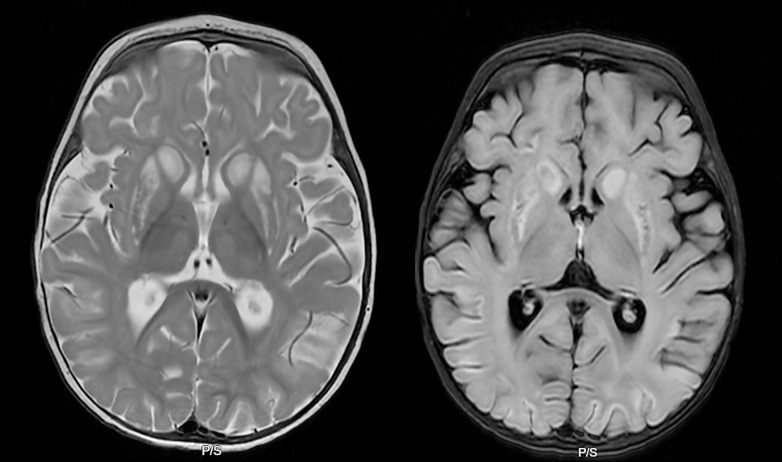

Case presentation: Our case is a 7-month-old female infant who presented with a 3-week history of irritability, altered behavior, and refusal of newly introduced solid foods. Symptoms started with an upper respiratory tract infection, followed by lethargy, floppiness, and abnormal movements. The patient was admitted to the pediatric ward with a broad differential diagnosis. Extensive laboratory evaluations revealed lactic acidosis. MRI brain showed symmetric restricted diffusion affecting the bilateral basal ganglia, thalami, and cortical regions. Whole genome sequencing identified biallelic variants of the SLC19A3: a c.1364T>G p.Met455Arg missense variant in the maternal allele and a 2.3 kb deletion of intron 3 of the paternal allele. Both variants were identified as variants of uncertain significance. However, given the clinical picture, MRI brain findings, resolution of symptoms with empiric biotin and thiamine supplementation, and biallelic SLC19A3 variants of unknown significance, the patient most likely suffers from BTBGD. Patient continues to show sustained developmental progress on biotin and thiamine supplementation.